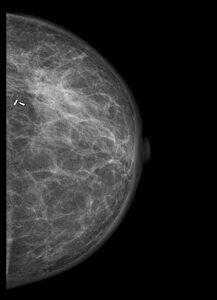

В операционной мы проводим контроль ширины краёв резекции на специальной рентгенологической установке:

Светлый поясок неизменённых тканей говорит о достаточной ширине отступа от опухоли.